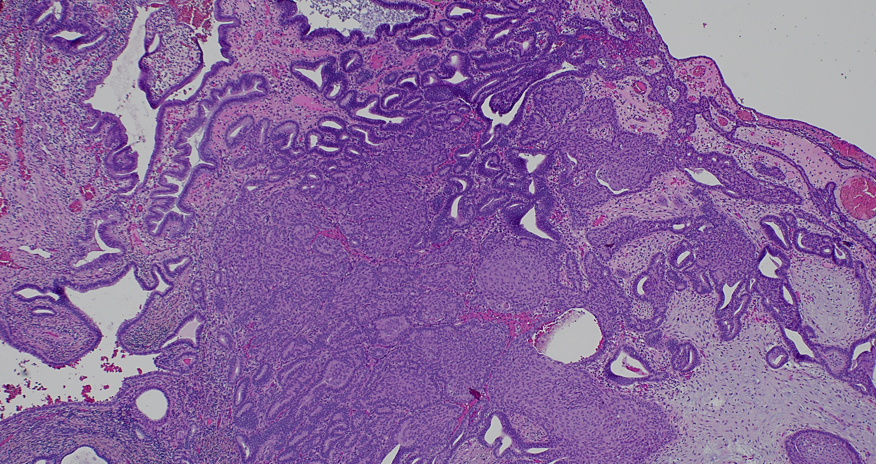

Atypical polypoid adenomyoma: biphasic lesion with crowded, architecturally complex endometrioid glands showing cytologic atypia, embedded in a myomatous stroma. Don’t overcall as carcinoma #PathTwitter #GYNpath